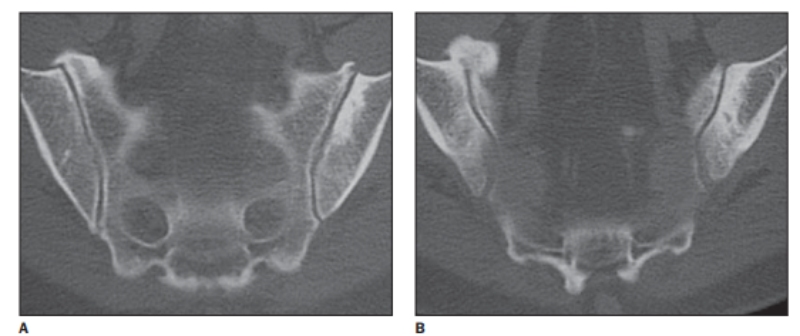

Hình ảnh Xquang viêm khớp cùng chậu

• Hình A – Mức độ 0 – Bình thường.

• Hình B – Mức độ 1 – Nghi ngờ: Có sự xuất hiện xơ cứng bề mặt khớp nhưng khoảng cách khớp vẫn bảo tồn.

Viêm khớp cùng chậu gây xơ cứng

Viêm khớp cùng chậu (hình A) gây xơ cứng và xói mòn dưới sụn (dấu mũi tên) và dính khớp (hình B)